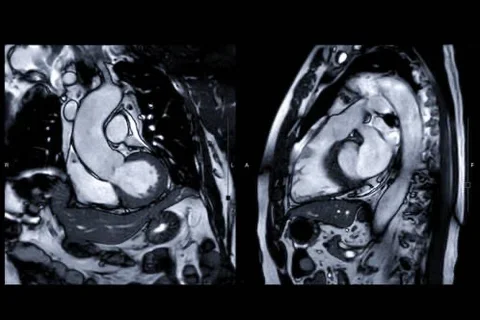

Cardiovascular Imaging

CV Imaging